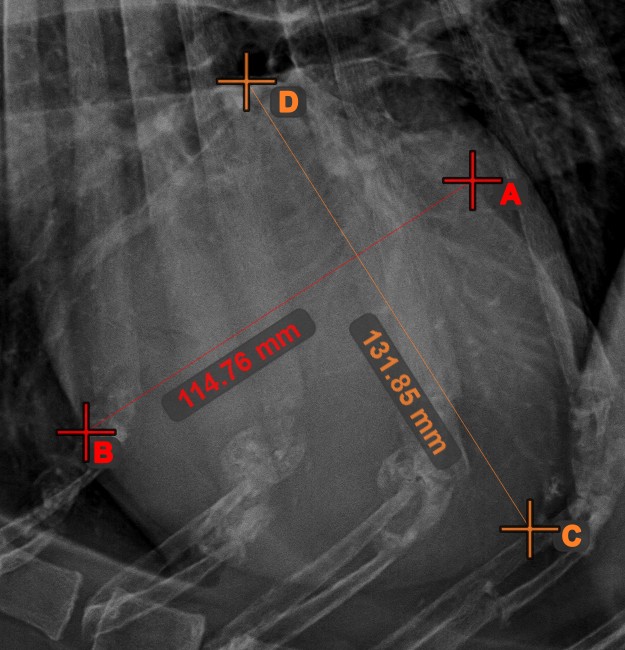

Linienmessung¶

Erstellen Sie eine Linienmessung, um den Abstand zwischen zwei Punkten mit hoher Genauigkeit zu berechnen.

Wählen Sie das Werkzeug Linienmessung aus und weisen Sie es einer der verfügbaren Maustasten zu. Setzen Sie die Start- und Endpunkte in der Szene oder wählen Sie sie aus bereits vorhandenen Punkten im Bild aus. Der Abstand zwischen den beiden Punkten wird automatisch anhand der Standardkalibrierdaten oder der durch die Längenkalibrierung-Messung neu kalibrierten Daten berechnet.

Ändern Sie den Start- und Endpunkt mit dem Werkzeug Objekt auswählen/verschieben. Der Abstand zwischen den beiden Punkten wird automatisch neu berechnet.